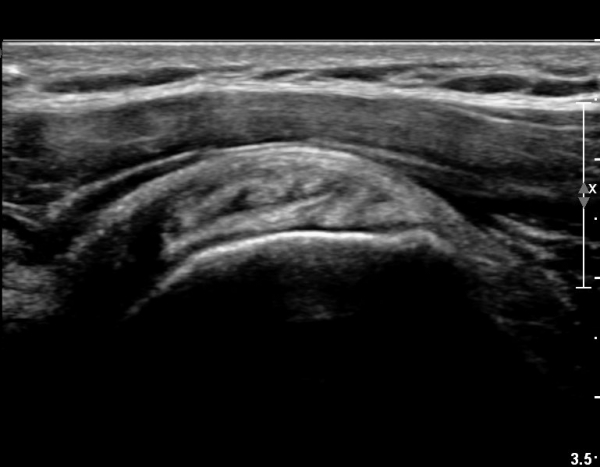

ÃÊÀ½ÆÄ ¼Ò°ß :  ȸÀü±Ù°³ °í¶û  °Ë»ç¸¦ À§ÇÑ »ó¿Ï Á߸³À§¿¡¼­ °ß°©ÇÏ±Ù°Ç °Ë»ç¸¦ À§ÇØ  ŽÃËÀÚ¸¦

¾à°£ ³»ÃøÀ¸·Î ±â¿ï¿© ½ÃÇàÇÑ °ß°©ÇÏ±Ù°Ç Á¾´Ü¸é°Ë»ç¿¡¼­ °ß°©ÇÏ±Ù°Ç »óºÎ°ÇÀÇ

Á¾¹æÇ⠺и®(½ÇÁú³» ÆÄ¿­)°¡ °üÂûµÈ´Ù(»çÁø 1).

ŽÃËÀÚ¸¦ Á¶±Ý ´õ ¸»´Ü¹æÇâ(caudal)À¸·Î À̵¿ÇÏ´Ï ÆÄ¿­ÀÌ ´õ¿í ¶Ñ·ÈÇÏ´Ù(»çÁø 2, 3).